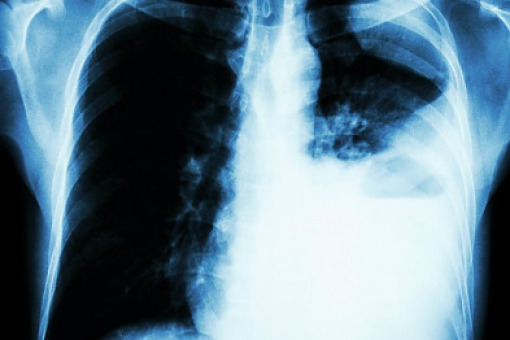

Zapraszamy do obejrzenia wykładu dr. Adama Płużańskiego na temat najnowszych doniesień z kongresu ASCO 2022 dotyczących leczenia ukierunkowanego molekularnie w niedrobnokomórkowym raku płuca.